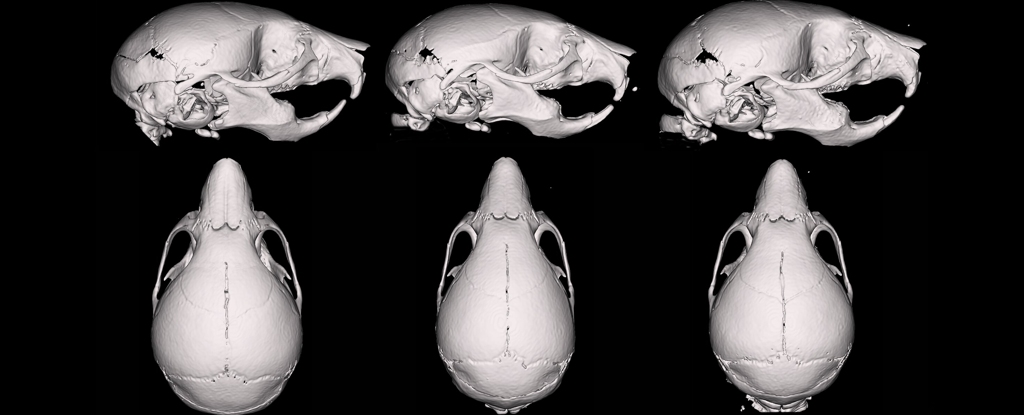

Después del nacimiento, los investigadores analizaron las crías: midieron sus cráneos y los reconstruyeron en 3D. En total nacieron 140 crías de 21 camadas.

Las crías expuestas a esa mezcla nacieron con cráneos y caras más pequeñas y estrechas. También tenían narices más cortas y menor peso corporal, aunque dentro del rango normal para su edad.

Cray explicó que vieron un estrechamiento general del rostro y del cráneo. Es un patrón que, según él, se parece a ciertas alteraciones observadas en niños humanos.